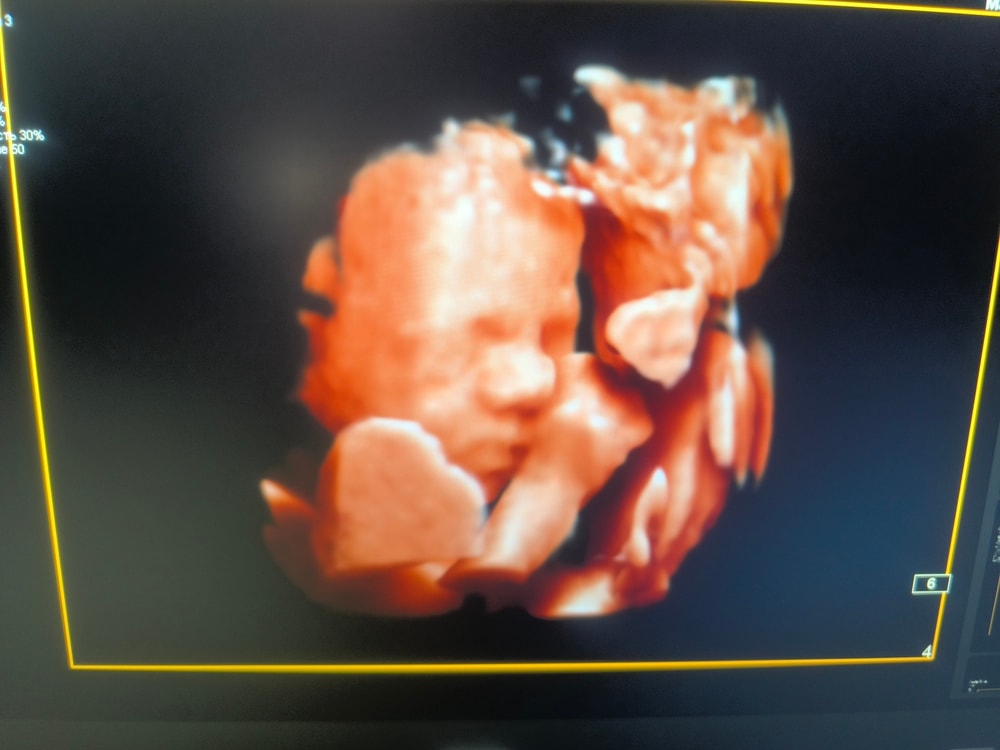

Узи 27и6 недель

Съездили сегодня на узи в Днк клиник по рекомендации девушки к Горяиновой . Оооочень понравилась, теперь она мой топчик. 😍

Бусинка наша 1097 гр. Все развито по срокам, все в норме 🙏Волос сказали мало пока, только только пушок вылез, но возможно вырастут еще, у старших детей длиннющие шевелюры были.

Так интересно наблюдать как дети там существуют ... Чудо техники все же 😀